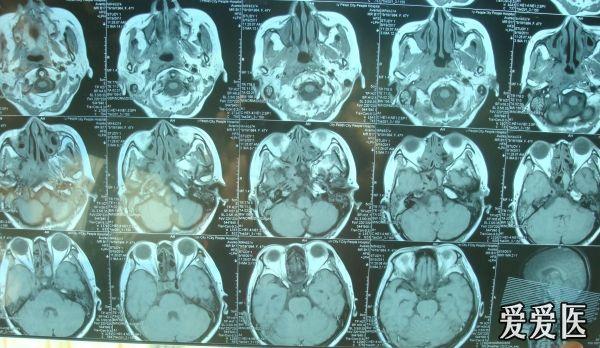

周围颅底骨质及颅内软组织的侵犯情况,对鼻咽癌肿瘤的分期有指导意义

鼻咽癌 - 肿瘤医学专业讨论版 - 爱爱医医学论坛 - 爱爱医医学网